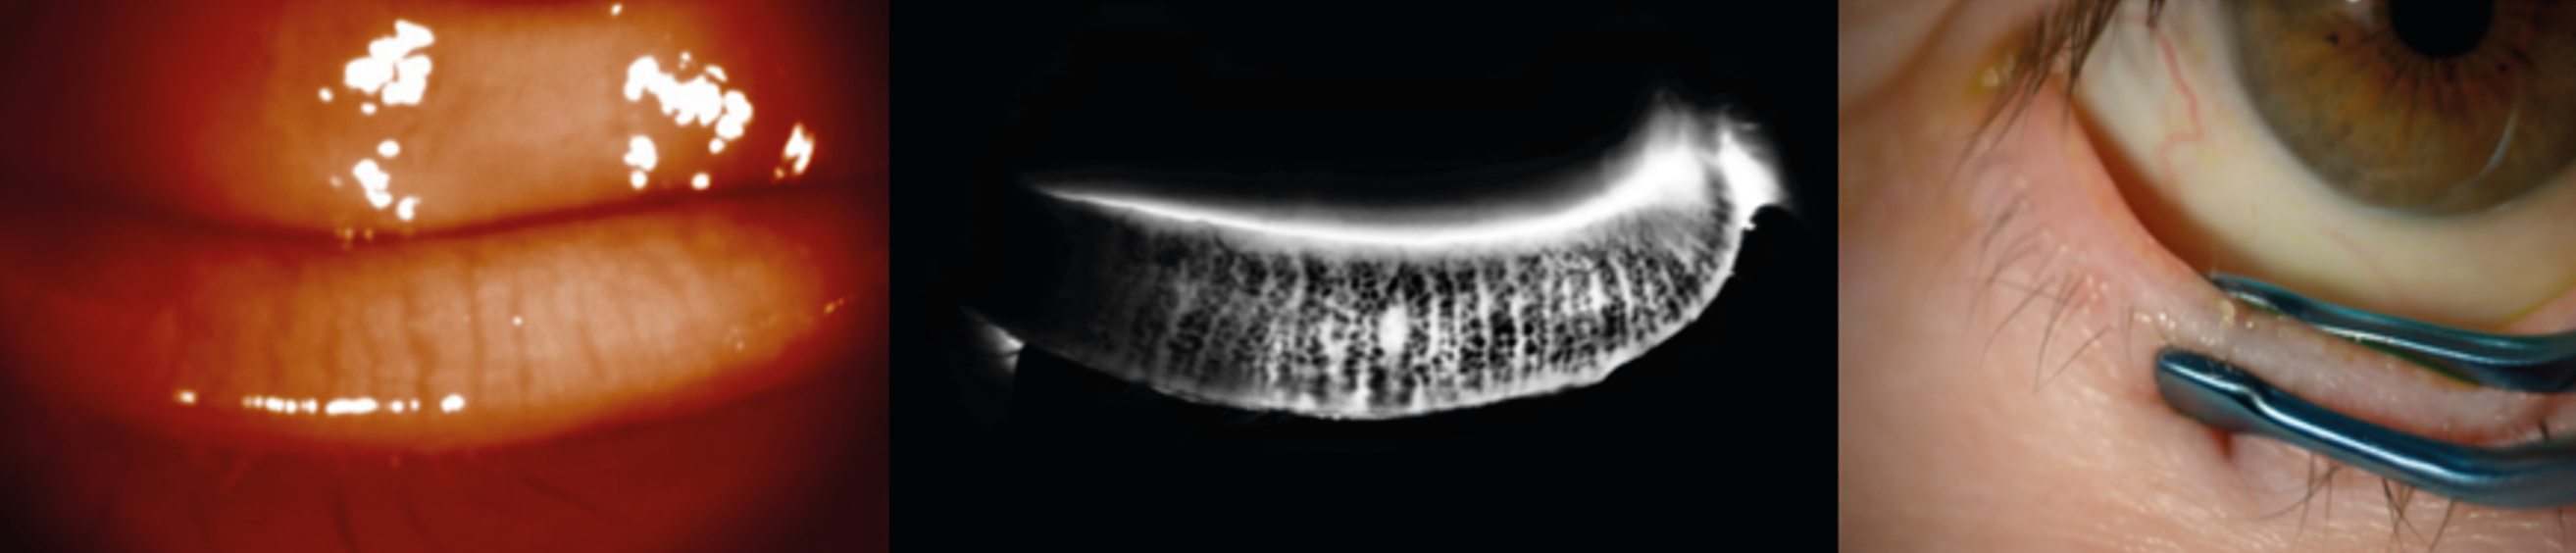

Figure 3. A. Taches de Bitôt OD/OG au moment du diagnostic en lumière blanche, puis en lumière bleue avec instillation de fluorescéine : notez l’aspect « vers luisants » de la conjonctive temporale.

B. Disparition des taches à 3 mois de la supplémentation vitaminique OD/OG.